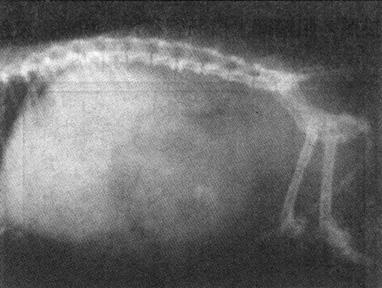

2)脱位 对半脱位和深在性脱位,临床诊断较为困难,须进行X线检查。全脱位的X线表现为关节内两骨端的关节面对应关系完全脱离(图1-2)。半脱位的X线表现是相对应的关节面部分脱离,失去正常相互平行的弧度和间隙。先天性脱位多见于膝关节,X线显示股内踝关节面平坦,外滑车发育不良等。

图1-2 猫左膝关节脱位合并右胫骨近端骨折

侧位显示左膝关节正常位置发生改变,左胫骨向前移位。右胫骨近端骨折、移位重迭,骨干有骨裂